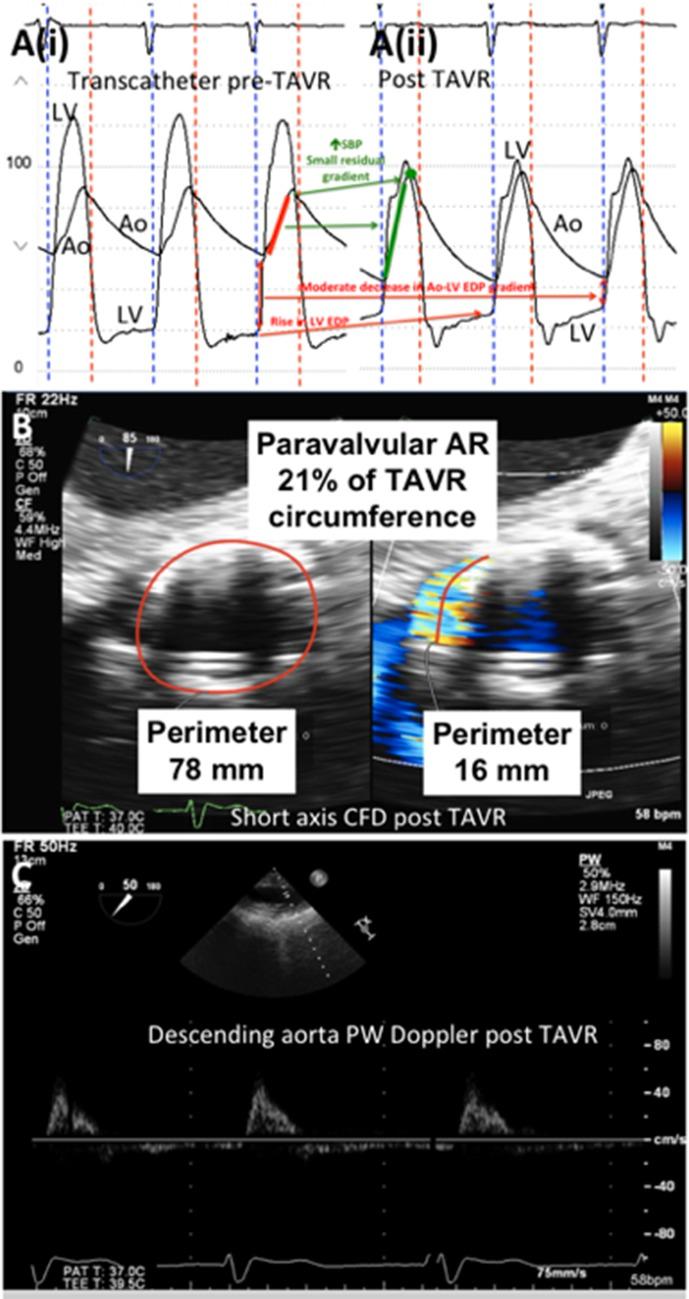

Transcatheter aortic valve replacement (TAVR) has become the preferred therapy for treatment of severe aortic stenosis in patients at intermediate to high risk of perioperative mortality following surgical aortic valve replacement. Haemodynamic assessment is an integral part of the procedure, and it is crucial for the operator to have an in-depth understanding of the haemodynamic alterations that occur during balloon aortic valvuloplasty and transcatheter valve deployment. Comprehension of the haemodynamic tracings is also pivotal for early recognition of periprocedural complications. With expanding indications for TAVR, it is imperative for members of the structural heart team to have an in-depth, nuanced understanding of transcatheter haemodynamic waveforms and their correlation with echocardiographic Doppler waveforms that are obtained periprocedurally during TAVR. This review provides a collection of transcatheter haemodynamic tracings and their corresponding Doppler echocardiography correlates that are demonstrative of physiological alterations and pathological lesions (complications) that occur during TAVR.